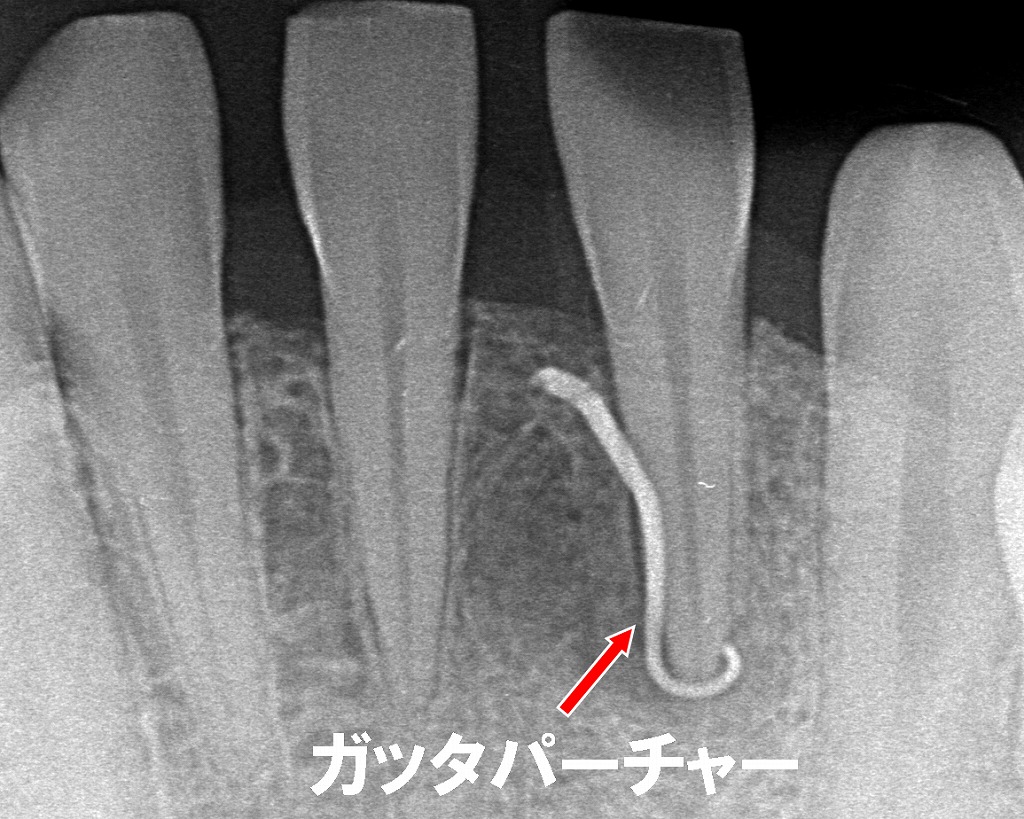

フィステル(瘻孔)は、**歯の中や根の先で炎症が起き、溜まった膿の出口として歯ぐきにできる“排膿の通り道”**です。

写真のように小さな白っぽいふくらみ・ニキビのような形で現れ、押すと膿が出ることもあります。

虫歯がない左下1番の内部で感染が起きています。

膿の原因となっている感染源を正確に示しています。

■ 今起きている状態(写真の解説)

- フィステル:根の先でできた膿が歯ぐきから出てきている状態

- 原因歯(左下1番):虫歯は無いが、内部の歯髄が壊死し根尖に感染が広がっている可能性が高い

膿が出ているため痛みが軽減することもありますが、根の先に感染が残っている限り治癒はしません。

原因歯の内部を清掃・消毒し、感染源を取り除く治療です。

フィステルは、原因を除去すると数日〜数週間で自然に消失します。